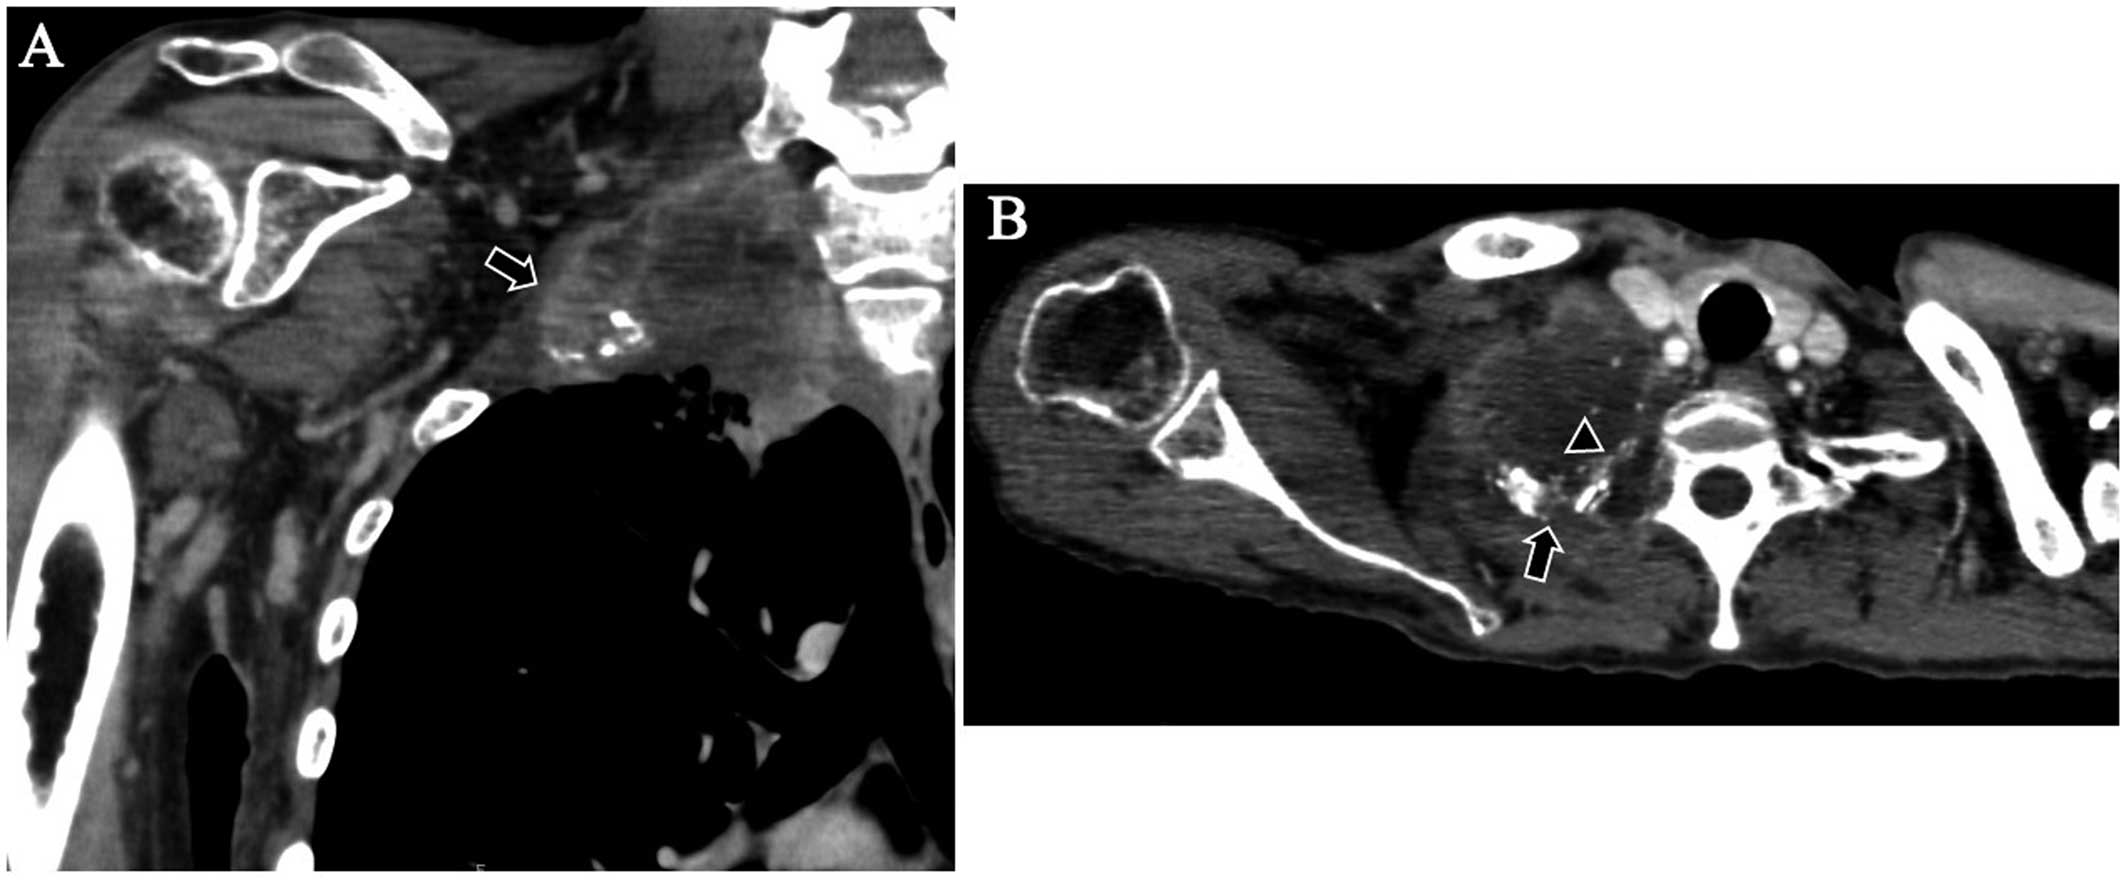

Palliative sequential chemoradiotherapy for pulmonary sulcus tumor: A case report

Pulmonary sulcus tumors are occasionally encountered in non‑small-cell lung cancer (NSCLC) patients. If the patients have a good clinical condition, concurrent chemoradiotherapy is indicated. However, palliative chemotherapy and chemoradiotherapy for patients exhibiting a poor overall condition have not been reported to date. We herein report the case of a 54‑year‑old female patient with a pulmonary sulcus tumor, who had a poor performance status. The patient received sequential chemoradiotherapy, with no severe complications. There was no local recurrence until the time of death, 8 months after the initiation of therapy. Palliative sequential chemoradiotherapy for pulmonary sulcus NSCLC must be effective and carry low risk of complications. Palliative sequential chemoradiotherapy may be considered in certain patients with pulmonary sulcus NSCLC. Either chemotherapy or radiotherapy is administered first and, if there is no apparent deterioration of the patient's general condition, the next treatment modality is administered.

Figure 1